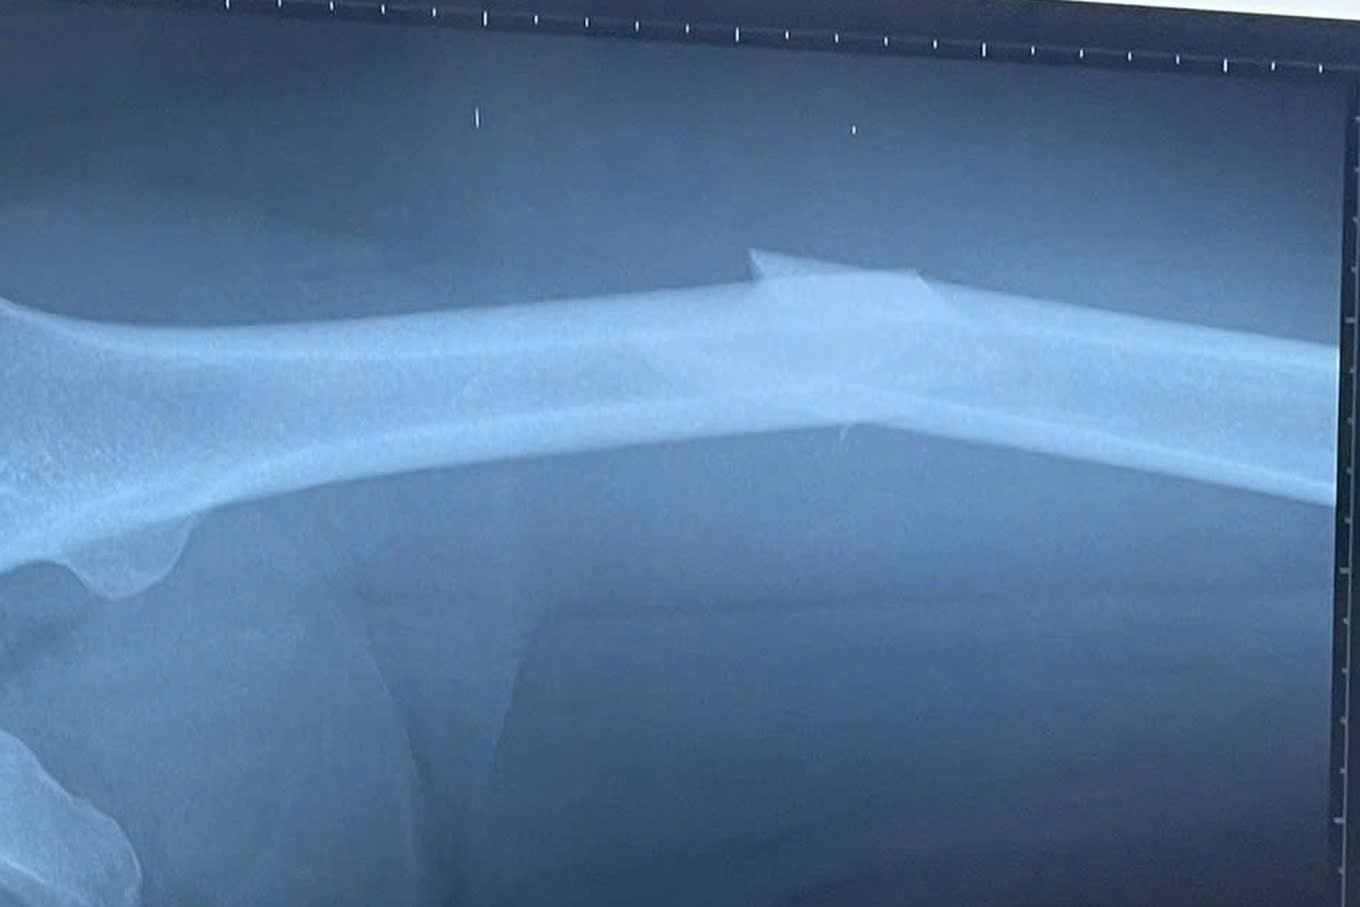

Chú thích ảnh

Ảnh chụp tình trạng gãy xương của Kỳ Hân (Ảnh: BV cung cấp).